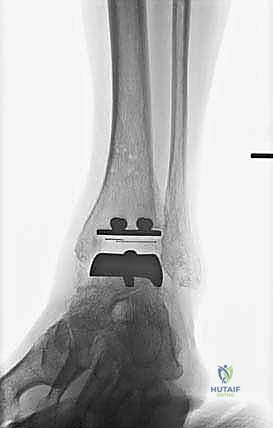

تتكون غرسة STAR من ثلاثة أجزاء رئيسية ولا تستخدم الأسمنت العظمي (Cementless)، بل تعتمد على النمو العظمي الدقيق داخل مسام الغرسة لتثبيتها بشكل دائم:

- المكون الظنبوبي (Tibial Component): صفيحة معدنية مسطحة من سبائك الكوبالت والكروم (Cobalt-Chromium)، تُثبت في أسفل عظمة الساق (الظنبوب) بواسطة أسطوانتين معدنيتين تدخلان في العظم لضمان الثبات المطلق.

- المكون الكاحلي (Talar Component): قطعة معدنية تغطي قبة عظم الكاحل، مصممة بشكل تشريحي منحني يحاكي تماماً شكل العظمة الأصلية، وتحتوي على أخدود طولي.

- الحشوة البلاستيكية المتحركة (Mobile Polyethylene Bearing): هذا هو سر نجاح غرسة STAR. هي قطعة من البلاستيك الطبي عالي الكثافة (UHMWPE) توضع بين القطعتين المعدنيتين. هذه القطعة ليست ثابتة، بل تنزلق بحرية للأمام والخلف، وتسمح بدرجة طفيفة من الدوران. هذا التصميم "المتحرك" يقلل بشكل هائل من إجهاد القص (Shear Stress) على واجهة العظم والمعدن، مما يقلل من احتمالية تخلخل الغرسة (Loosening) على المدى الطويل، ويمنح المريض نطاق حركة فسيولوجي مذهل.

تُعد هذه الجراحة من أروع وأدق الإجراءات في عالم جراحة العظام. يقوم الأستاذ الدكتور محمد هطيف وفريقه الطبي في صنعاء بتنفيذها وفق بروتوكول عالمي صارم لضمان نسب نجاح تقارب 100٪. فيما يلي تفصيل دقيق لخطوات العملية، مدعوماً بالصور من داخل غرفة العمليات.